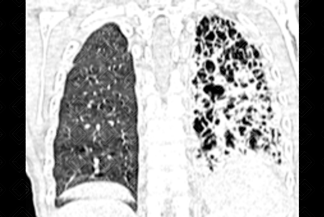

Texto alternativo para a imagem Créditos: Dra. Elazir Mota - Rio de Janeiro/RJ.

Descrição da imagem: Sinal do anel em sinete, que corresponde ao diâmetro interno do brônquio, aparece maior que o diâmetro do vaso pulmonar adjacente (artéria), como indica a caixa vermelha na figura.

• Tomografia computadorizada do tórax: D etecta-se bronquiectasia quando o diâmetro interno do brônquio aparece maior que o diâmetro do vaso pulmonar adjacente (artéria), descrito com sinal do anel em sinete (primeira imagem).